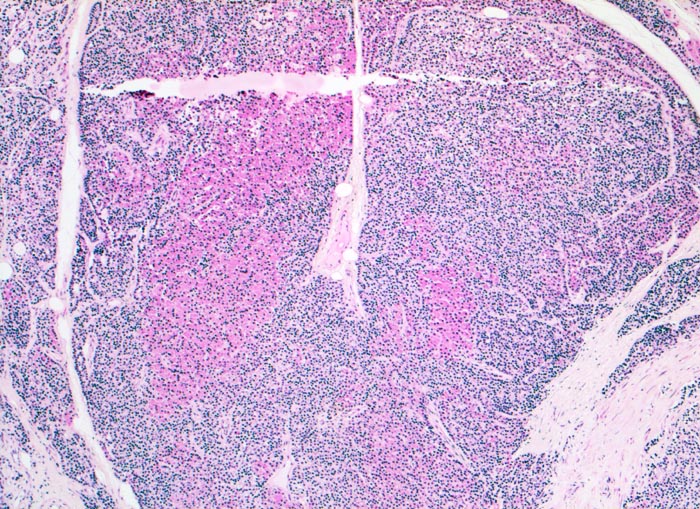

noduläre Nebenschilddrüsenhyperplasie

Knotiges Parenchym ohne Fettzellen. Die Knoten sind durch Septen voneinander abgegrenzt. Die Knoten bestehen aus Hauptzellen und onkozytären (roten) Zellen.

Der Patient leidet an einer chronischen Niereninsuffizienz. Die glomeruläre Filtrationsrate ist auf 25% reduziert. Unter anderem ist eine Hypokalzämie und eine Hyperphosphatämie vorhanden. Die Serumkonzentration des Parathormons ist erhöht. Die Diagnose eines sekundären Hyperparathyreoidismus wird gestellt.

Histologie

50